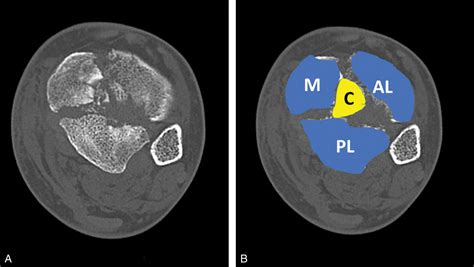

CT Scans

Computed Tomography (CT) scans offer detailed images of the bones and can help identify complex fractures and other bony abnormalities. CT scans are particularly useful for preoperative planning in cases requiring surgery.